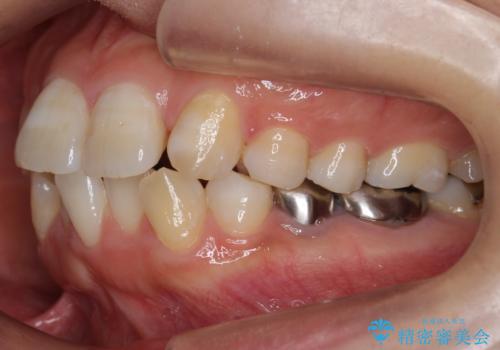

奥歯を後ろに下げて、前歯を並べています。

マウスピースと矯正用のミニスクリューを使用して治療しています。

銀歯も白くということでしたので虫歯治療も一緒に行っています。

左上7の根の治療や左下56銀歯の治療なども行いました。

右下7は根管治療をおすすめしましたが、患者様のご希望により抜歯となり、そのスペースを利用して下の前歯をならべています。